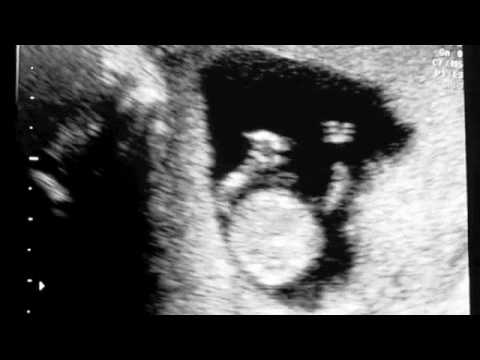

This is our first and our families live half a world away from us (literally, they're in New England and we're in China) so we took a little video of our 11wk ultrasound to share with them.

Seeing the little bean jump around like that makes everything about pregnancy feel a little more real!